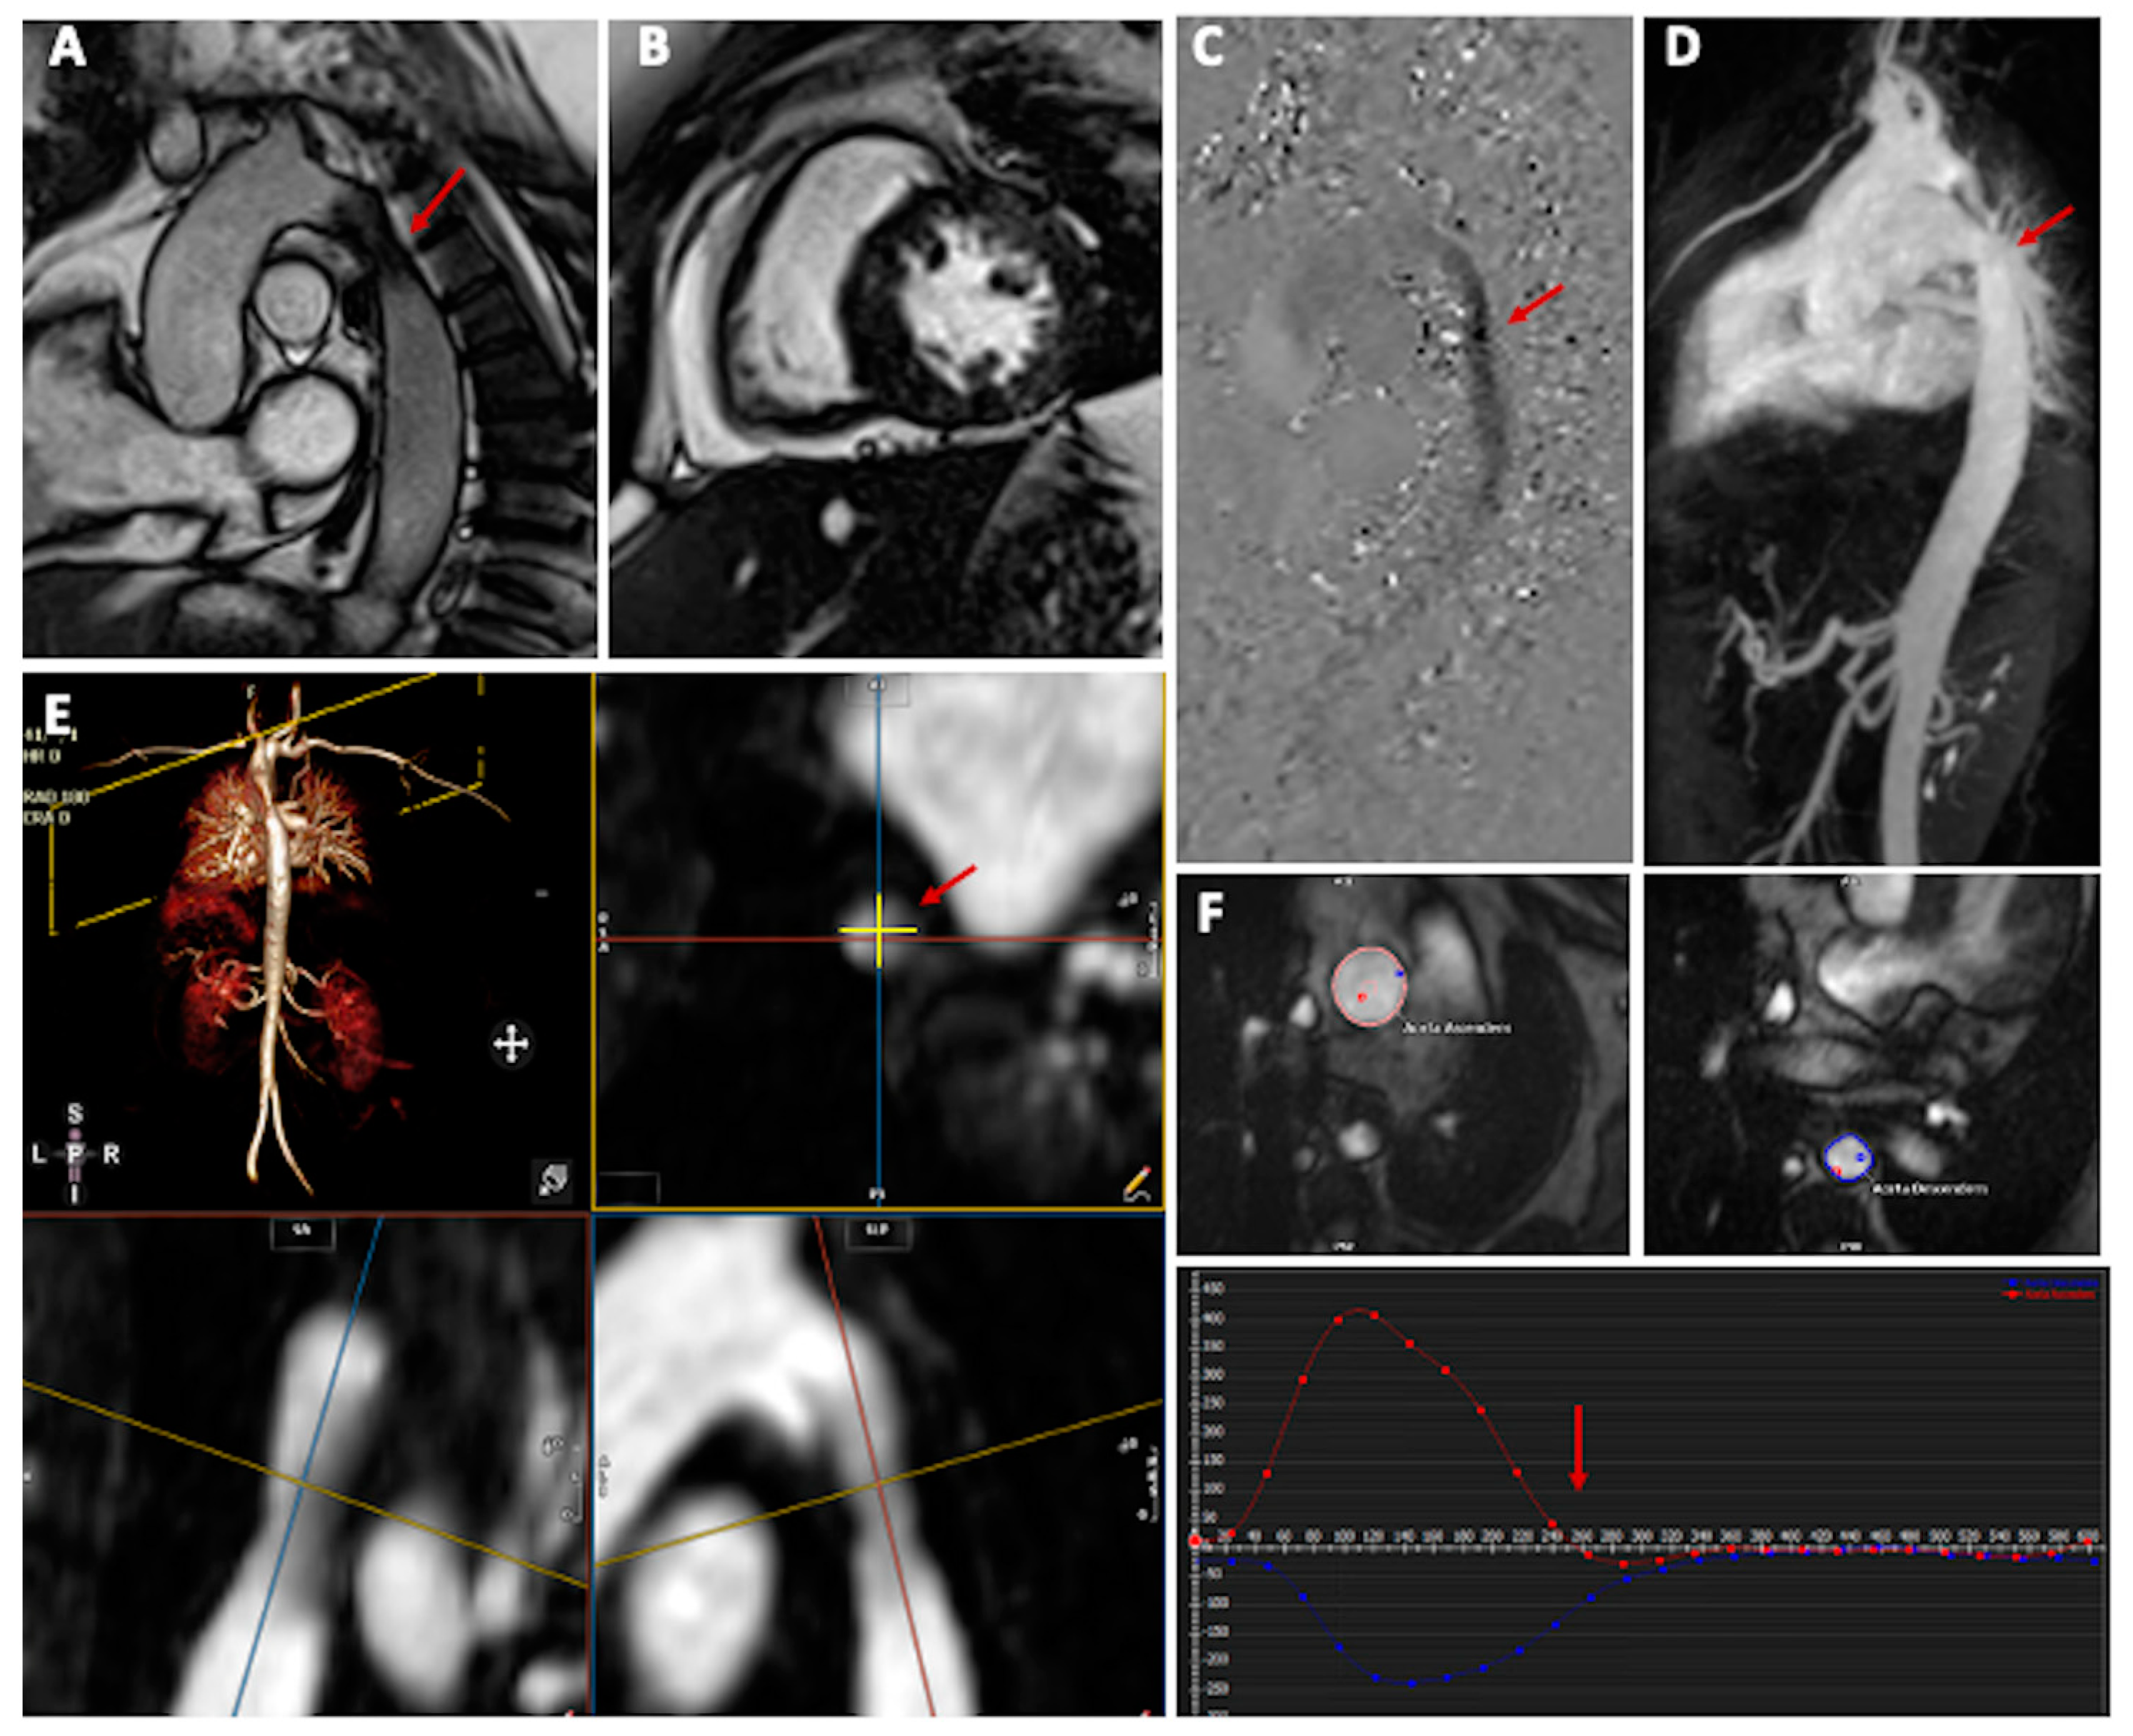

3. Cardiovascular Magnetic Resonance